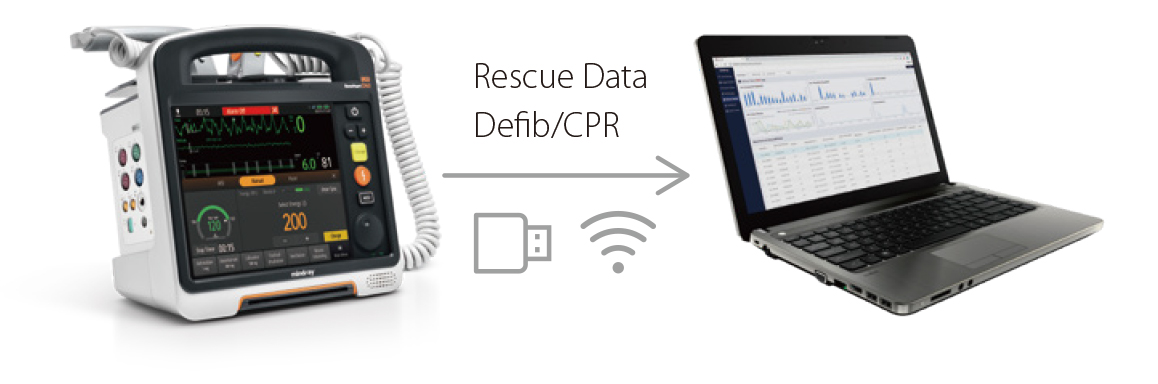

- Les protocoles de dĂŠbriefing structurĂŠs du D60 amĂŠliorent les performances des ĂŠquipes de rĂŠanimation lors de rĂŠanimations ultĂŠrieures.

DĂŠbriefing structurĂŠ

- Les protocoles de dĂŠbriefing structurĂŠs du D60 amĂŠliorent les performances des ĂŠquipes de rĂŠanimation lors de rĂŠanimations ultĂŠrieures.